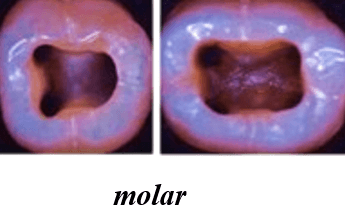

Shapes of the access cavity of all teeth

| Tooth | Access cavity shape | Average depth |

|---|---|---|

| Maxillary incisors | Triangular or oval (placed over the palatal surface) |

3-4 mm |

| Mandibular incisors | Triangular (placed over the lingual surface)

|

3-4 mm |

| Maxillary canines | Oval (placed over the palatal surface)

|

4-5 mm |

| Mandibular canines | Oval (placed over the lingual surface)

|

4-5 mm |

| Maxillary premolars | Oval or rounded (located over central part of the tooth)

|

4-5 mm |

| Mandibular premolars | Oval (over central of the tooth, slightly to the lingual)

|

4-5 mm |

| Maxillary molars | Trapezoidal (located over the mesial buccal cusp or the central part of the tooth)

|

5-6 mm |

| Mandibular molars | Trapezoidal or rhomboidal (centered over the mesial buccal cusp)

|

5-6 mm |

| Maxillary second molars | Trapezoidal (centered more mesially and palatally, slightly off-center) | 5-6 mm |

| Mandibular second molars | Trapezoidal or rhomboidal (centered over the mesial buccal cusp) | 5-6 mm |

| Maxillary third molars | Oval or trapezoidal | 5-7 mm |

| Mandibular third molars | Trapezoidal | 5-7 mm |